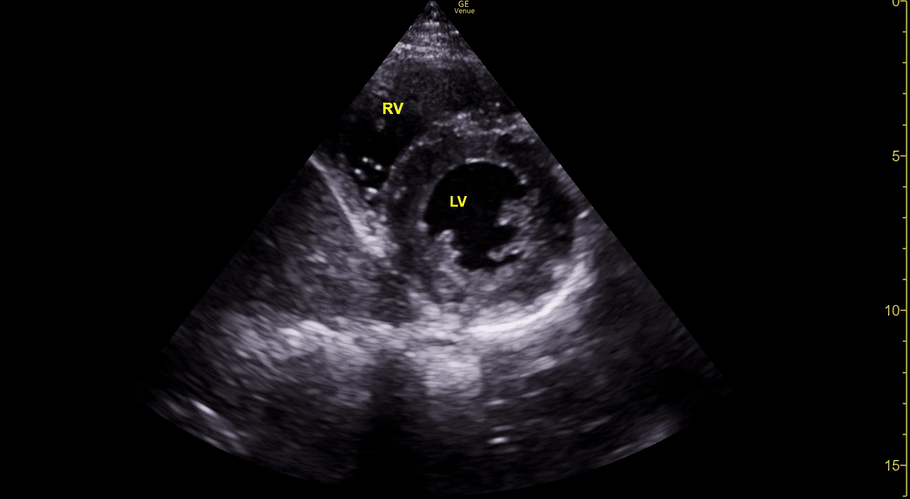

Equality: is the RV dilated or significantly impaired?

Normally, the RV is a low-pressure, thin-walled, high-compliance chamber that wraps anteriorly around the muscular, cone-shaped LV. The normal RV : LV diameter ratio is 0.6 : 1.

When the pulmonary artery pressure rises, the RV will dilate, altering the normal RV:LV ratio. Although sacrificing sensitivity, the use of equality (1:1 ratio) as a cutoff can achieve a specific estimation of RV strain. If imaged correctly by a trained operator, the presence of an RV:LV ratio > 1 is highly specific for RV strain.

RV dilation can be acute, chronic, or acute-on-chronic. However, in patients presenting with undifferentiated chest pain, shortness of breath, hypotension or syncope, the presence of any RV dilation should raise suspicion for acute pulmonary embolism (PE). Furthermore, in a patient in shock, the presence of RV strain may signal the need for aggressive therapy – emergency thrombolysis.

THE VIEWS

The A4C view provides an accurate chamber size comparison. However, achieving a proper A4C view (avoiding foreshortening or ballooning, and visualising the four chambers with a vertically oriented interventricular septum) can be a challenging exercise of image acquisition. Additionally, the PSAX view at the level of the papillary muscles shows both LV and RV side by side and is useful to assess function and size. When RV pressure is high, the septum will be pushed and flattened towards the LV, resulting in the characteristic “D-shaped” LV or “D sign”.

PITFALLS

When comparing size, beware of correct image acquisition, as oblique planes lead to misinterpreting the RV:LV ratio. For apical views be sure to slide the probe sufficiently laterally on the chest wall so that it lies over the true apex. Also, be sure to obtain a real horizontal plane, avoiding foreshortening (ballooning). For the PLAX view it is useful to fan through the heart’s long axis, making sure that LV visualization is maximized relative to the RV. Furthermore, an understanding of probe placement and marker orientation conventions is fundamental. If inadvertently scanning in reverse orientation, the normally larger LV could be mistaken for an abnormally enlarged RV.